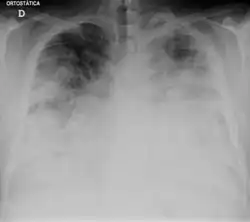

Legionelóza neboli legionářská nemoc je akutní horečnaté onemocnění vyvolané gramnegativními bakteriemi rodu Legionella, nejčastěji bakterií Legionella pneumophila, které postihuje především dýchací cesty. Nejzávažnějším a zároveň nejčastějším projevem je zápal plic („legionářská nemoc“). Dalšími projevy infekce může být lehké chřipkové onemocnění s bolestmi hlavy a svalů bez postižení plic („pontiacká horečka“).